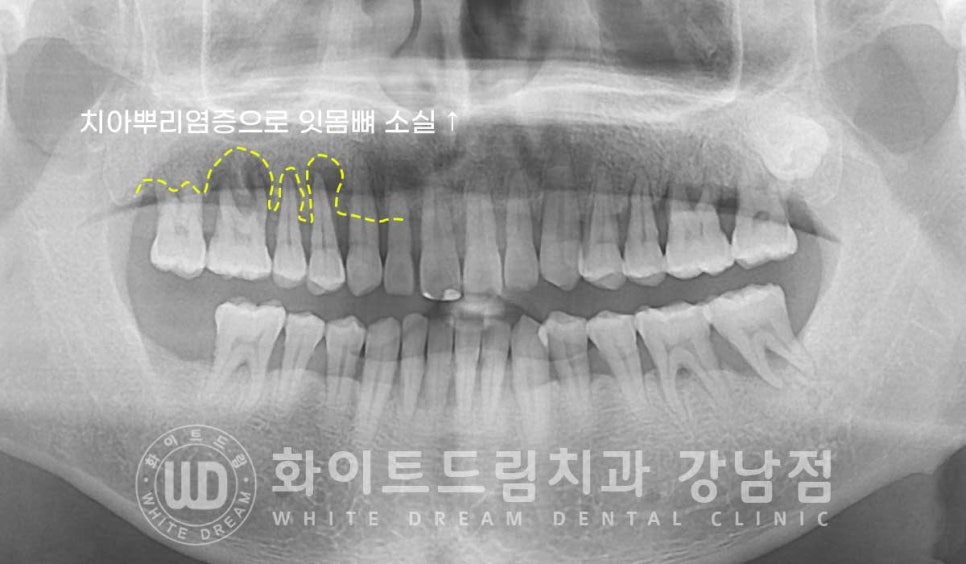

전체적으로 잇몸뼈가 치주염으로 크게 내려앉아있는 상태로

10번대 치아 주위 잇몸뼈를 보면 검은색으로

치아 뿌리 주위에 동그랗게 표기된 부분이 보일 겁니다.

x-ray 상에서 밀도가 낮을수록 이렇게 검은색으로 나타납니다.

원래는 잇몸뼈가 있어 하얗게 보여야 하는 부위인데

잇몸뼈가 녹고 그 자리에 액체(고름)이 차있는 상태라고 보시면 되겠습니다.

이 치아들은 잇몸뼈가 아닌 고름이 치아의 대부분을 잡고 있는 상태로

동요도 검사 시에도 심하게 상하좌우로 흔들리고 있는 것이 확인되었고

환자분도 식사를 할 때마다 통증과 치아의 흔들림이 느껴지신다고 하여

발치 즉시 임플란트 치료를 진행하기로 치료 계획을 세웠습니다.